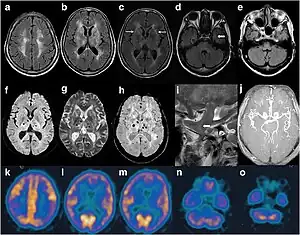

| Cranial imaging of an FFI patient. In the MRI, there are abnormal signals in the bilateral frontoparietal subcortical area. MRA showed smaller distal branches of cerebral arteries. | |